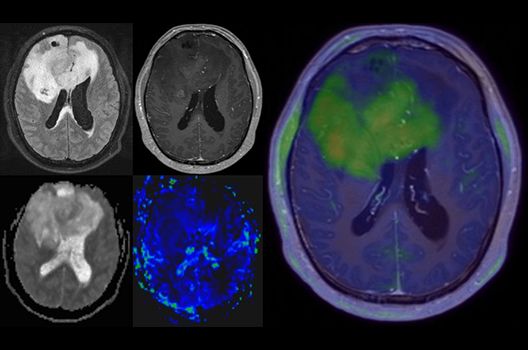

Die Hybridbildgebung mittels PET/MRT spielt insbesondere in der onkologischen Bildgebung eine wichtige Rolle. Eine mögliche Fragestellung ist die Unterscheidung zwischen einem Tumorrezidiv oder therapeutisch assoziierten Veränderungen insbesondere dann, wenn diese Frage mittels MRT alleine nicht beantwortet werden kann.

Die bildgebende Diagnostik und Verlaufsbeurteilung von Tumoren des Nervensystems ist einer der klinischen und Forschungsschwerpunkte unserer Abteilung. Eine besondere Bedeutung kommt der Hybrid-Bildgebung zu. Das Universitätsklinikum verfügt über einen integrierten Ganzkörper-PET/MRT-Scanner, der die Vorteile der MRT-Bildgebung und der Positronenemissionstherapie (PET) vereinigt. Aufgrund der langjährigen klinischen Arbeit und Forschungstätigkeit mit diesem Gerät hat die Neuroradiologie Tübingen maßgeblich zur Etablierung dieses Verfahrens beigetragen. Auch weiterhin forschen wir intensiv an neuen Methoden zur frühen Einordnung von Tumoren und insbesondere Tumorrezidiven, die mit anderen Methoden häufig nicht erfasst werden können.